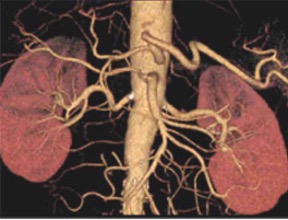

CT検査

体を透過したX線を多方向から収集し、コンピューター処理によって輪切り(断層)画像を作成する装置です。脳、肺、肝臓、膵臓、血管などの臓器や、小さい病変も鮮明に描出できます。病変の正確な位置や大きさを三次元(3D)に把握することが可能で特にがんの発見、脳卒中、外傷による骨折や内臓の損傷など迅速で精密な診断が求められる場面で不可欠な検査です。

当院では2024年にキヤノン製Aquilion PrimeSPを導入しました。このCTは、Ai技術を用いた画像再構成技術AiCE を採用し、X線量を抑えつつノイズを低減し、シャープで高コントラスト・高精細なCT画像を生成することが可能です。

撮影した画像をコンピューター処理して立体的な画像として表示できます。